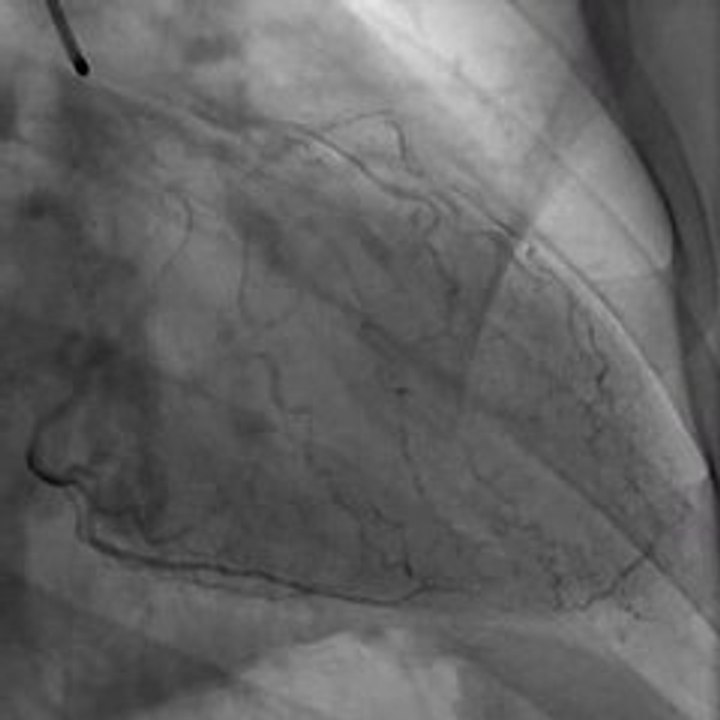

Cardiac CT Angiography Program

Angiography or arteriography is a medical imaging technique used to the inside, or lumen, of blood vessels and organs of the body, with particular interest in the arteries, veins and the heart chambers. @ http://docturs.com/dd/pg/videos/play/group:2355/2567/cardiac-ct-angiography-program